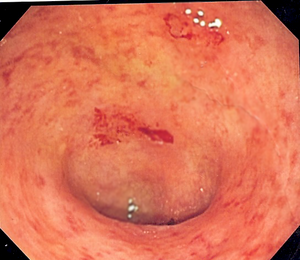

Небезпечним симптомом вважаються випорожнення з наявністю крові в калі. Своєрідне свідчення серйозних захворювань:

- хронічні захворювання у вигляді хвороби Крона і виразкового коліту.

Виразковий коліт